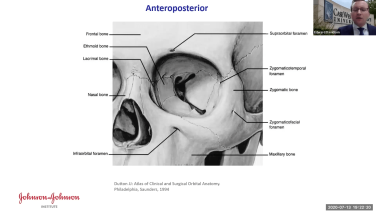

Concepts in Orbital Reconstruction: Anatomy with Edward Davidson, MD